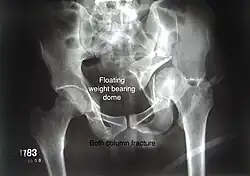

Combined both column fractures | These are the most complex injuries. Here the weight bearing roof or dome of the acetabulum is a floating piece. This adds to complexity of management.

All three x-ray views plus CT scan is a must for diagnosis and management of this complex injury.

Like any other acetabular fracture, if the femoral head is dislocated out of the socket, early reduction into socket is a priority. However, in this injury, non-operative treatment rarely gives satisfactory results. Surgical management is ideal. The choice of approach rests with the surgeon, but going from front, or anterior approach is must. The posterior injury may be tacked with anterior approach by experienced surgeon. If the patient is unfit to undergo major surgery due to any reason, longitudinal traction to achieve secondary congruence of hip may help to restore hip function, though partially. |

Both column fracture showing floating weight bearing dome -